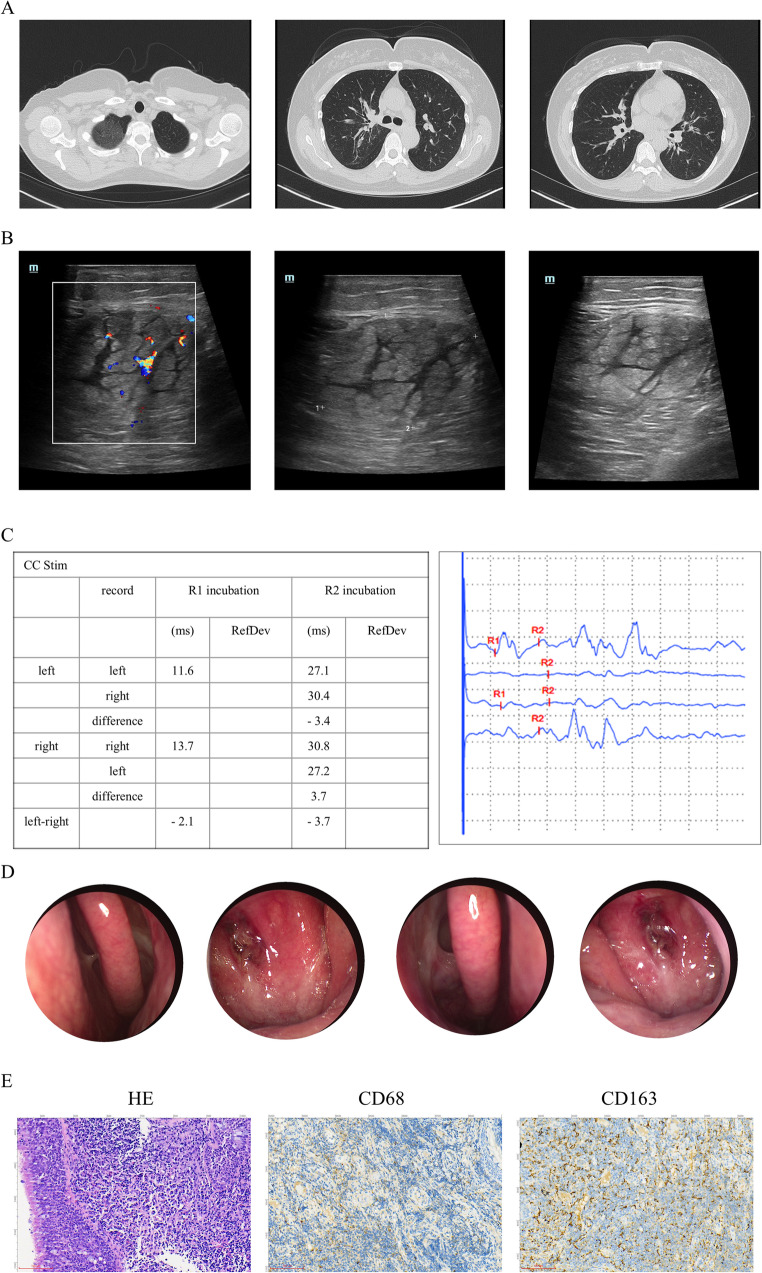

目的:嗜酸性肉芽肿病合并多血管炎(EGPA)是一种罕见的血管炎,其特征是人体组织和外周血中嗜酸性粒细胞增多。在本病例中,我们报告了一位53岁的EGPA女性患者。通过本病例和文献复习,我们希望对EGPA的早期表现、诊断和处理进行阐述,有助于临床医生了解该病,重视dupilumumab诱发EGPA的可能性,提高EGPA的早期诊断率,减少误诊和漏诊。方法:采用美国风湿病学会(American Rheumatology Association, ACR) 2022年制定的EGPA诊断标准;这些标准包括临床表现、实验室检查和病理活检。此外,我们对该病例进行了全面的文献综述。结果:我们报告了一位53岁的女性患者,她在接受dupilumab治疗难治性哮喘和鼻窦炎后出现了严重的周围神经性疼痛。患者的症状、实验室检查结果和鼻咽活检病理结果共同支持EGPA的诊断。当dupilumab转为mepolizumab联合糖皮质激素时,她的周围神经性疼痛和哮喘症状明显缓解。我们的文献综述也提供了Dupilumab和EGPA之间关系的详细讨论。结论:我们报告了一例EGPA合并Dupilumab引起的周围神经性疼痛,mepolizumab对该患者有良好的治疗效果。我们的文献综述显示,虽然dupilumab治疗嗜酸性气道炎症性疾病是有效的,但临床医生必须注意dupilumab诱导或加重egpa的可能性。

Purpose: Eosinophilic Granulomatosis with Polyangiitis (EGPA) is a rare vasculitis characterized by increased eosinophils in human tissues and peripheral blood. In this case, we present a 53-year-old female patient with EGPA. By this case and literature review, we want to explain the early manifestations, diagnosis, and management of EGPA, which will help clinicians to understand the disease and attach importance to the possibility of dupilumab-induced EGPA, to improve the early diagnosis rate of EGPA, and reduce misdiagnosis and missed diagnosis.

Methods: The diagnostic criteria for EGPA established by the American Rheumatology Association (ACR) in 2022 were used; these criteria encompass clinical presentation, laboratory tests, and pathological biopsy. In addition, we conducted a comprehensive literature review on this case.

Result: We present a 53-year-old female patient who developed severe peripheral neuropathic pain after the administration of dupilumab for the treatment of refractory asthma and sinusitis. The patient's symptoms, laboratory examination findings, and nasopharyngeal biopsy pathology results collectively support the diagnosis of EGPA. When dupilumab was converted to mepolizumab combined with glucocorticoid, her peripheral neuropathic pain and asthma symptoms were dramatically relieved. Our literature review also provides a detailed discussion on the relationship between Dupilumab and EGPA.

Conclusion: We present a case of EGPA with peripheral neuropathic pain induced by Dupilumab, and mepolizumab has a good therapeutic effect on this patient. Our literature review shows that although dupilumab is effective in treating eosinophilic airway inflammatory diseases, clinicians must pay attention to the possibility of dupilumab inducing or aggravating EGPAs.